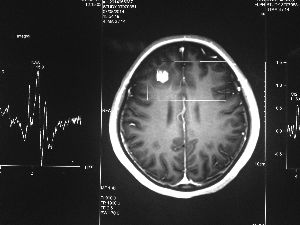

方框亮點為CT片顯示的異物

今年6月份,張敏在宿舍休息時,又發(fā)起了癲癇,也是口吐白沫,渾身抽搐。送到蘇州一家大醫(yī)院,頭顱核磁共振檢查出,張敏大腦右額葉處有一處病灶,也就是大腦額頭處有個東西。

腦袋里的東西,到底是腫瘤還是其他什么東西,這個謎像個石頭一樣,壓得張敏一家人喘不過氣。7月份,張敏一家又來到南京腦科醫(yī)院求醫(yī),第三次檢查后,醫(yī)生覺得很像是寄生蟲。不過,影像的檢查,只能作為醫(yī)生推測的依據(jù),具體是什么,只有手術拿出來后才能知道。

8月14日,張敏上了手術臺進行開顱手術。術中,楊坤將白色像棉線一樣的異物夾出來后,最初還沒有意識到是什么東西?!胺旁谑中g臺上的時候,它竟然動起來了,我當時就想到,這是寄生蟲。”楊坤說,“我們量了一下,蟲子有3厘米長?!?/p>